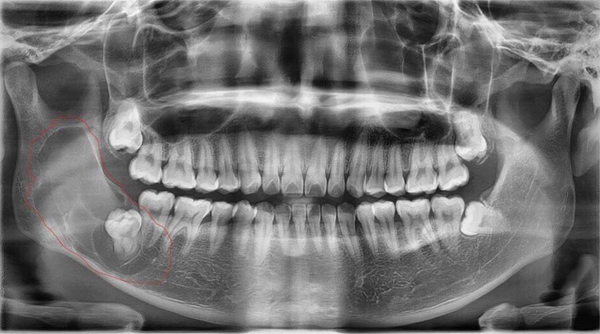

Như trường hợp của bệnh nhân T.Q.S (42 tuổi) ở phường Hồng Hải, TP Hạ Long, đi khám do sưng đau nhiều vùng má phải cách đây 1 tháng. Kiểm tra đánh giá tại phòng khám Răng hàm mặt của khoa Khám chữa bệnh theo yêu cầu, bác sĩ thấy khối sưng to vùng mang tai phải, viêm cuống răng 17, răng số 18 lệch ngầm. Nghi ngờ tính chất phức tạp của khối u, bác sĩ chỉ định thực hiện siêu âm, chụp cắt lớp vùng hàm mặt kết hợp chọc hút sinh thiết cho kết quả ung thư biểu mô tuyến nước bọt mang tai phải. Bệnh nhân được hội chẩn với Trưởng khoa Răng hàm mặt quyết định thực hiện phẫu thuật cắt u tuyến mang tai để kịp thời điều trị cho người bệnh. Sau ca phẫu thuật, bệnh nhân sức khỏe ổn định, vùng hàm mặt phải đỡ đau và sưng nề, được hội chẩn khoa Ung bướu để tiếp tục theo dõi điều trị sau mổ.

Để tạo nền tảng kỹ thuật cao hỗ trợ chẩn đoán chính xác và tăng hiệu quả điều trị cho người bệnh, phòng khám được đầu tư hệ thống cơ sở vật chất, máy móc, trang thiết bị đồng bộ, hiện đại từ những tập đoàn nha khoa uy tín trên thế giới, hỗ trợ đắc lực cho các bác sĩ thăm khám chẩn đoán, đánh giá toàn diện về răng, như: Máy X-quang răng toàn hàm Panorama, máy chụp cắt lớp vi tính đa dãy, máy chụp cộng hửng từ để khảo sát những bất thường vùng hàm mặt, chẩn đoán chính xác các khối u trong xương hàm, các răng mọc lệch ngầm, đo đạc xương giúp thực hiện chỉnh nha và cấy ghép implant một cách tốt nhất. Thời gian tới, bệnh viện trang sắm đầu tư máy phẫu thuật siêu âm piezotome giúp giảm sưng nề, giảm đau sau phẫu thuật, nhờ vậy rút ngắn thời gian nằm viện điều trị cho người bệnh.